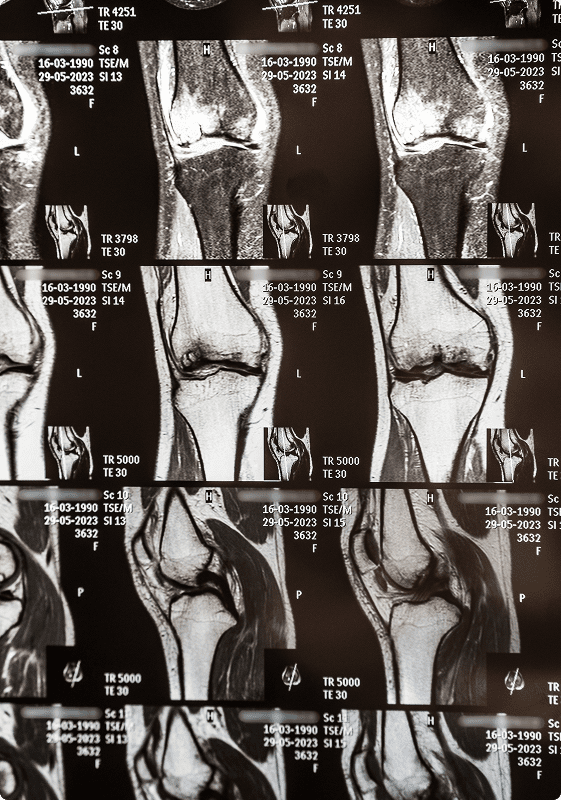

Initial treatment of an MCL injury is nonsurgical treatment including pain and swelling control. Crutches, a knee brace, and physical therapy may be recommended. If there is clinical suspicion of a complete tear or additional injury to the knee an MRI will be ordered.